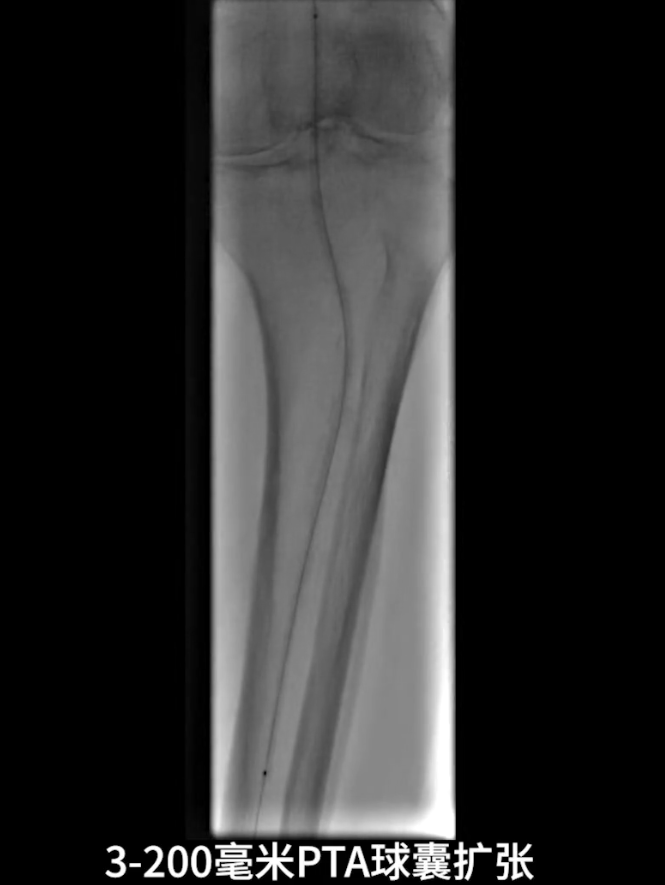

沿已建立轨道,选用4.0×150mm PTA球囊对股浅动脉闭塞病变段进行预扩张,为后续药物球囊治疗创造条件。

流出道扩张与优化:使用3.0×200mm PTA球囊对“胫腓干-腓动脉”全程进行扩张;